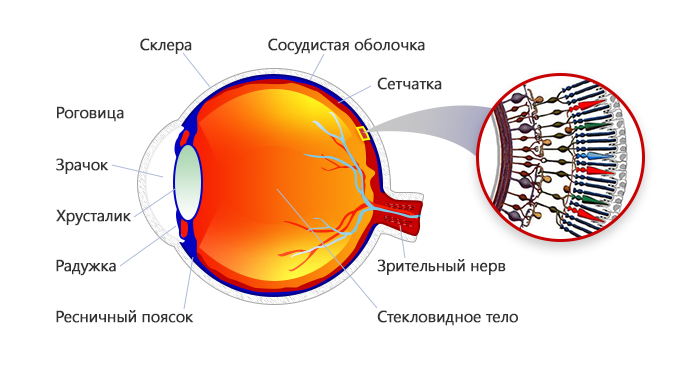

Изображения и анатомия сетчатки глаза

Раздел: Визуальный дайджест